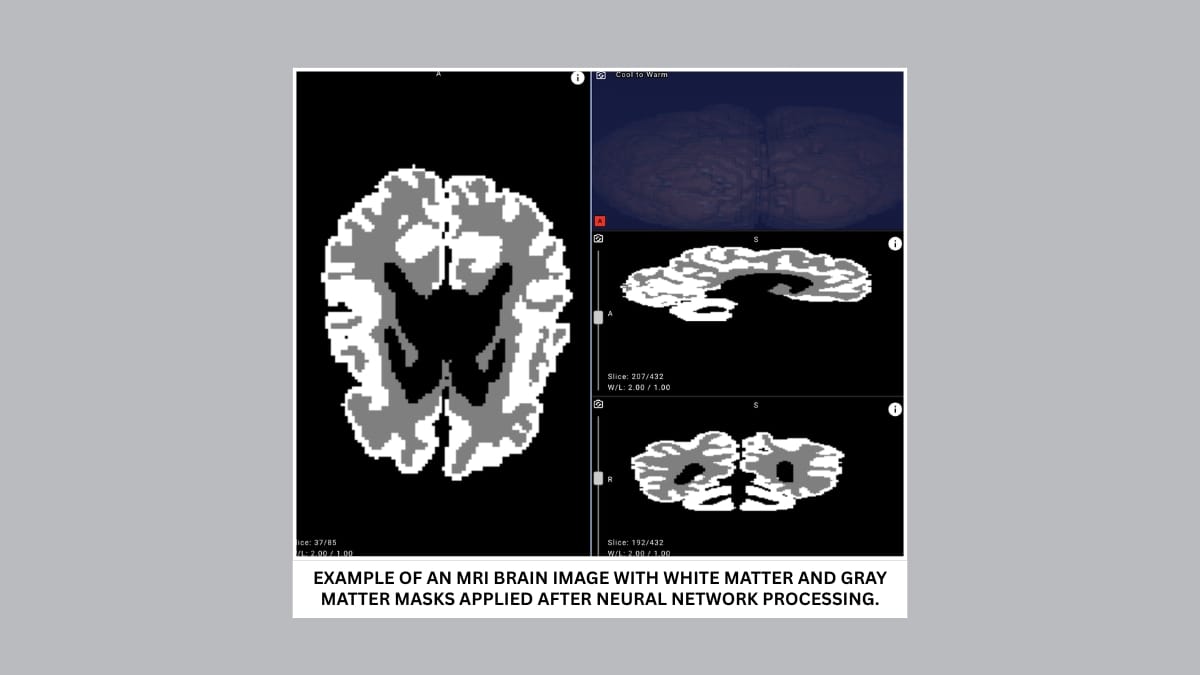

The proposed solution analyzes MRI scans and can distinguish between gray and white brain matter with over 90% accuracy. Cutting evaluation time from days to minutes, it enables earlier detection and more effective rehabilitation planning for infants with cerebral palsy and other central nervous system disorders.

Early diagnosis is critical for improving outcomes and ensuring effective rehabilitation. Yet detecting cerebral palsy within the first 12 months of life remains one of the most difficult tasks in modern medicine. An infant’s brain develops at a remarkable speed, and traditional MRI scans are difficult to interpret due to the low contrast between gray and white matter — the tissues that form the cerebral cortex and support higher brain functions.

The competition drew developers from around the world but also revealed a major obstacle: a lack of annotated data. In particular, segmentation masks — outlines of gray and white matter that are essential for training AI models for clinical use — were scarce. The iSeg-2019 dataset included only 15 annotated images, while the university’s archive contained MRI scans from 1500 patients without any annotations.

To bridge this gap, Yandex researchers collaborated with medical experts to create new annotations, design a dedicated neural network architecture, and run a series of machine learning experiments. The resulting model achieved over 90% accuracy in distinguishing gray and white matter in infant brains on internal evaluation data, demonstrating its potential for clinical use.

- Improve accuracy and objectivity. With over 90% accuracy, the model highlights outlines and quantifies the ratio of gray to white matter in an infant’s brain.